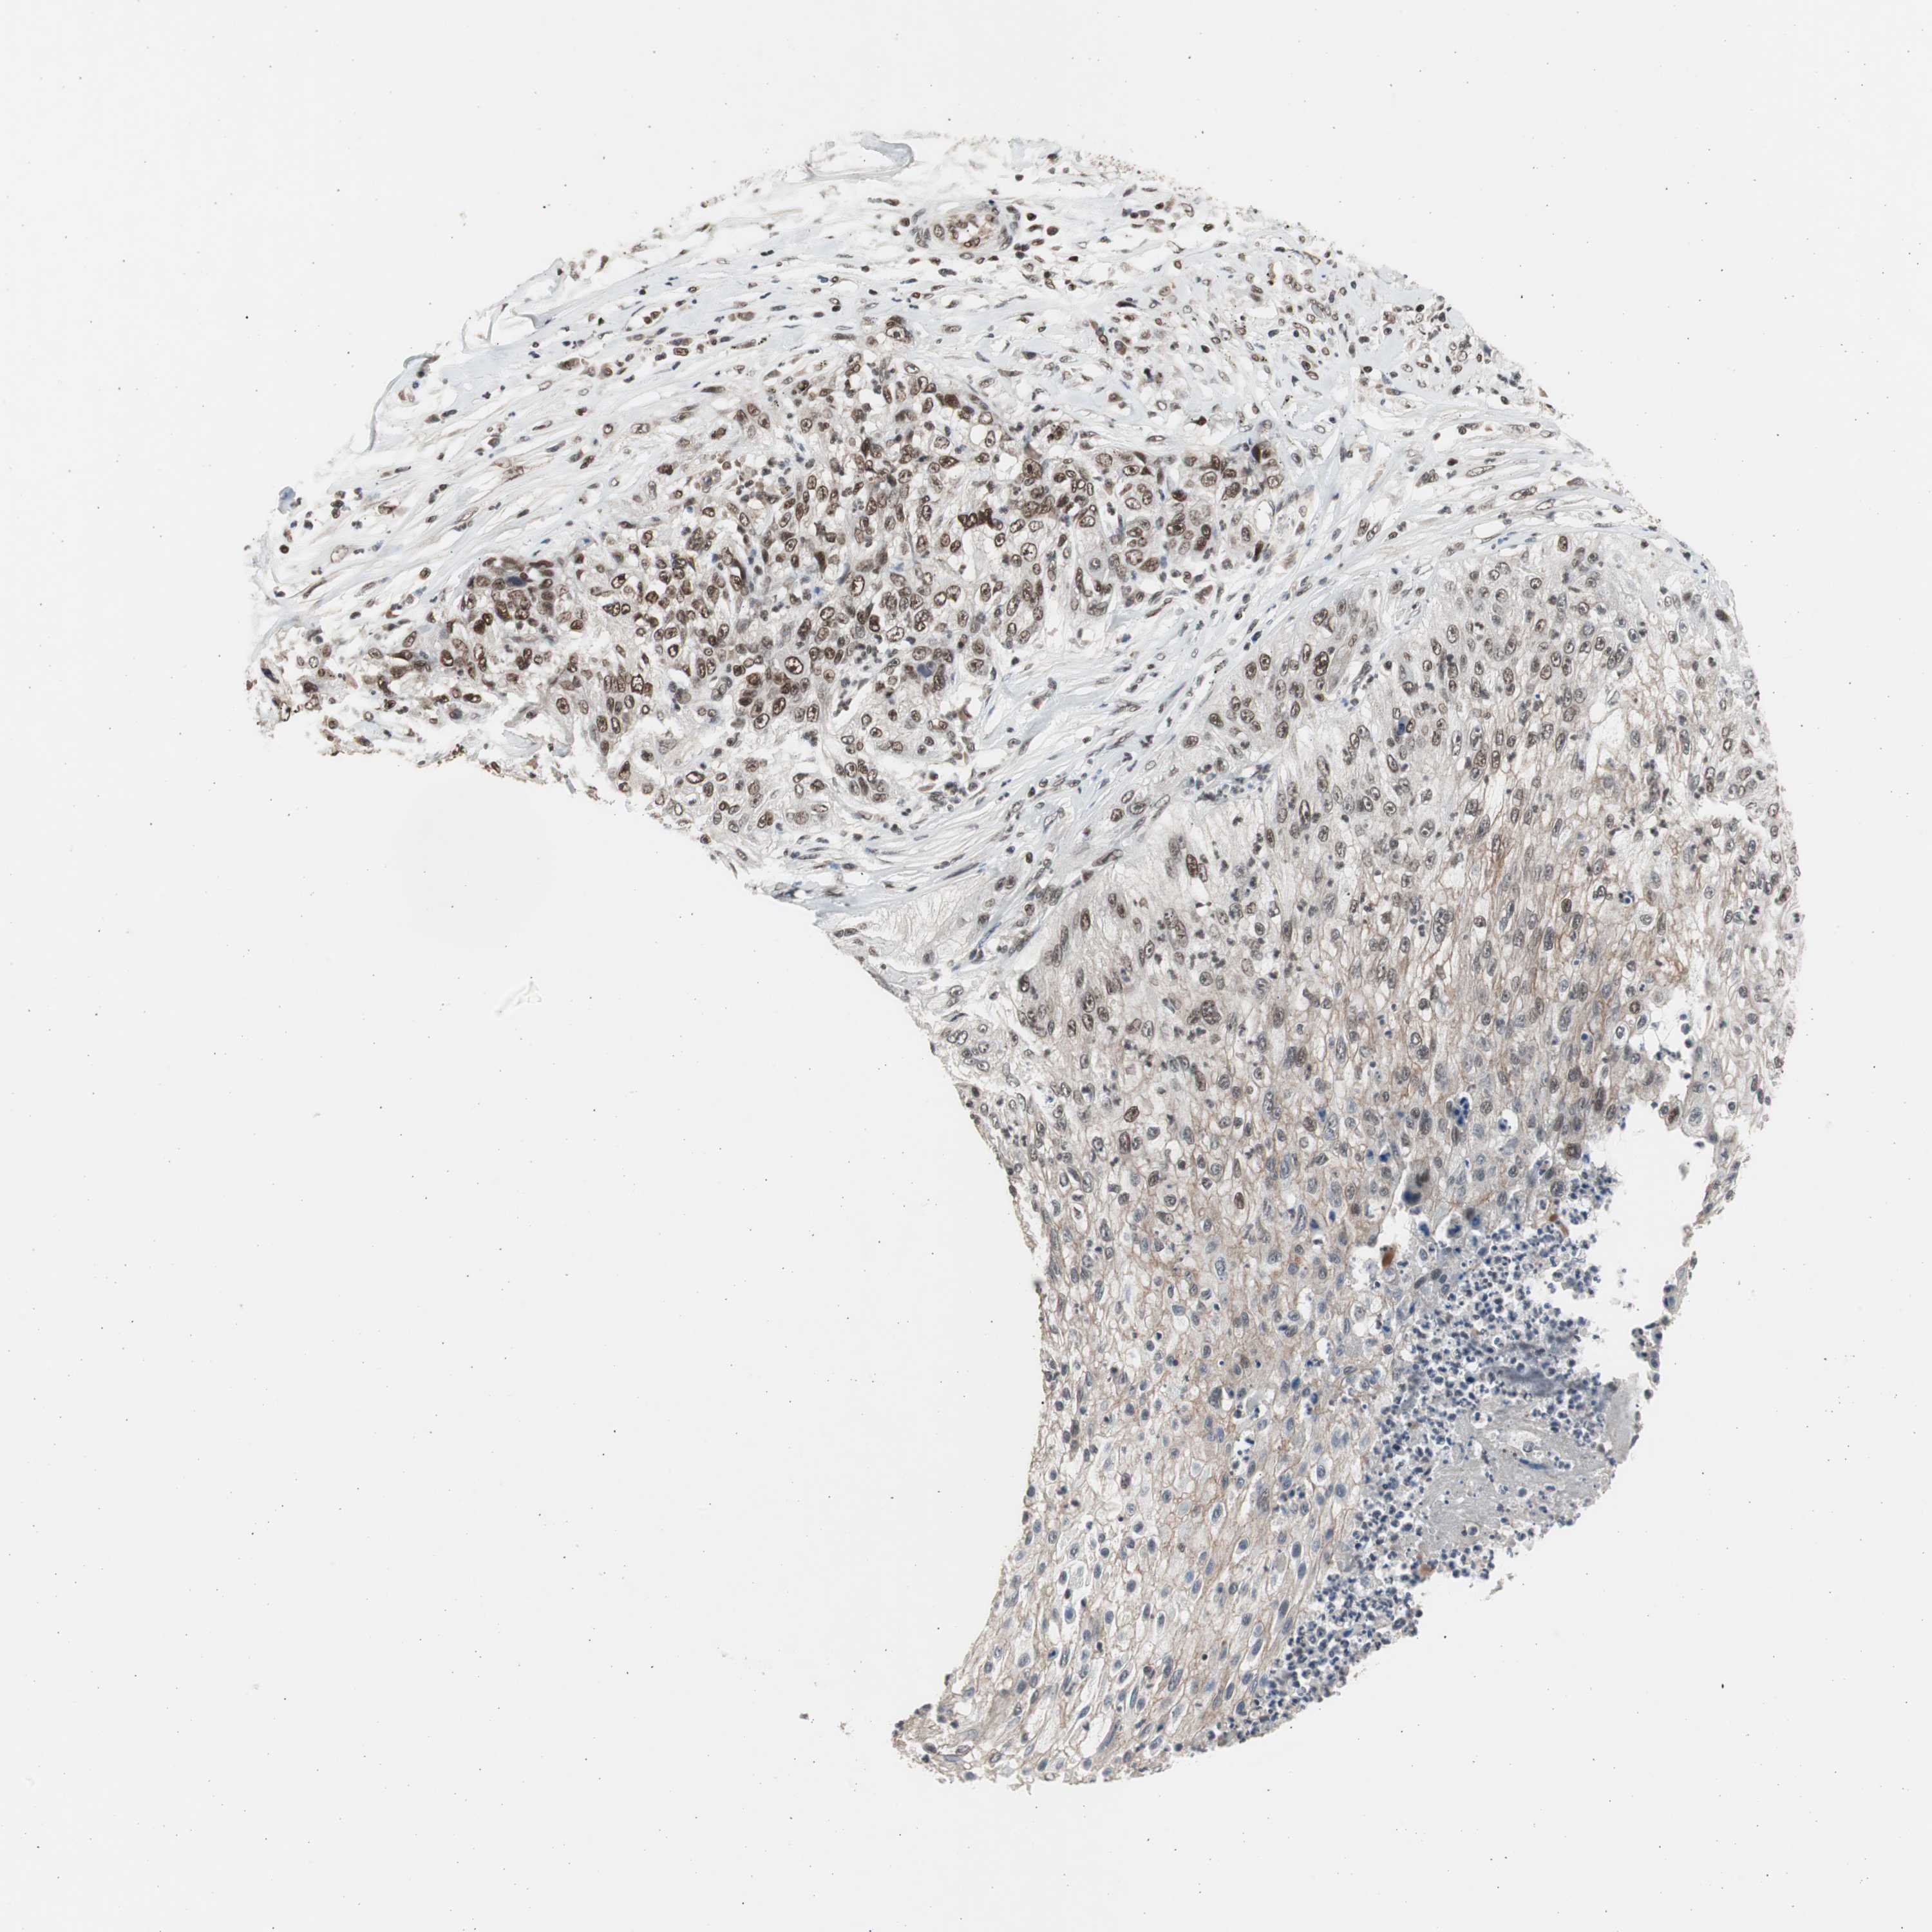

CANCER LUNG CANCER Show tissue menu